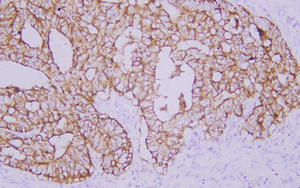

Immunohistochemistry analysis of paraffin embedded human colon carcinoma using Claudin 1 (GB14066) at dilution of 1: 200 |